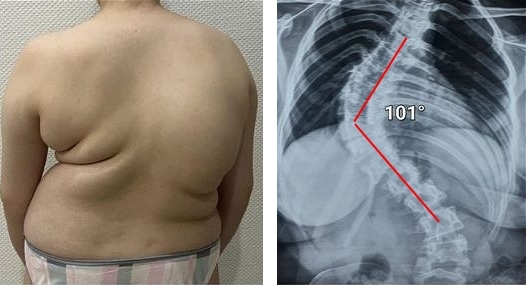

Tutte le articolazioni richiedono attenzione, ma la colonna vertebrale è la priorità. Occupatevene prima che inizino i cambiamenti irreversibili. Ecco cosa attende chi non ha prestato attenzione ai segnali del proprio corpo: ERNIA, SPOSTAMENTO DELLE VERTEBRE, DEFORMAZIONE DELLA COLONNA VERTEBRALE, CURVATURA DELLA SCHIENA, COMPLETA PERDITA DI MOBILITÀ. Non aspettate il momento in cui anche il semplice movimento diventerà una tortura!

Guardate queste fotografie. Ecco cosa è successo a coloro che non hanno fatto attenzione ai sintomi. Oggi queste persone sono completamente senza speranza, e molti di loro non hanno nessuno su cui contare per le cure. Volete davvero un destino simile?

— Ognuna di queste persone pensava che non sarebbe mai successo a lei! Ma ecco il risultato: perdita totale di mobilità, paralisi, amputazione — dipendenza a vita dall’aiuto altrui e LA SEDIA A ROTELLE! Più del 90% diventa disabile solo perché non ha preso le giuste misure in tempo. L’USURA DELLE ARTICOLAZIONI INIZIA IN SILENZIO — ignorare il dolore significa buttare la propria vita nel secchio!